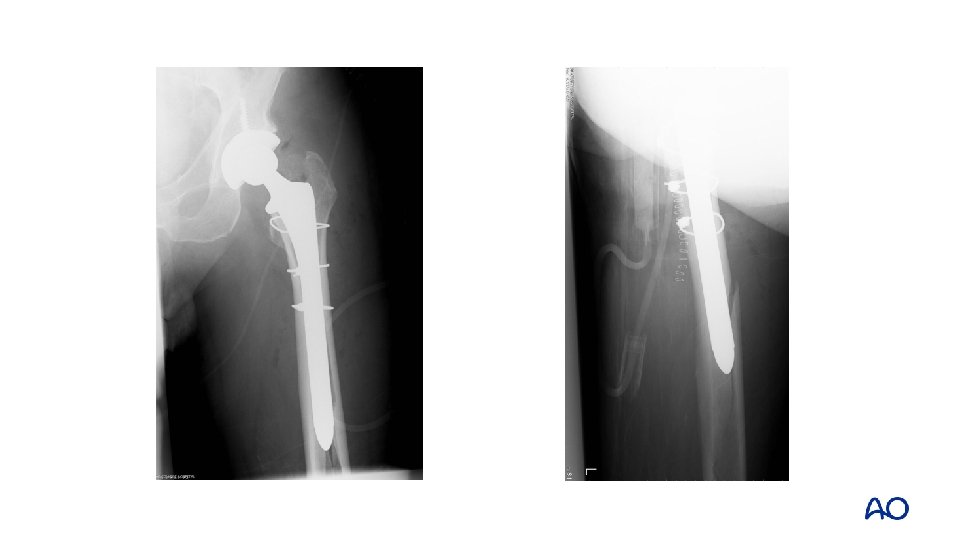

Case 7 • • • Proximal fracture through calcar and greater trochanter Uncemented stem with loss of fixation Vancouver B 2

Case 7 • • Fully coated long, straight stem Failure to ream full length of cylindrical stem

Case 7 • • Vancouver B 1 Fix without revision

Case 7 • • Healed at 6 months Persistent limp